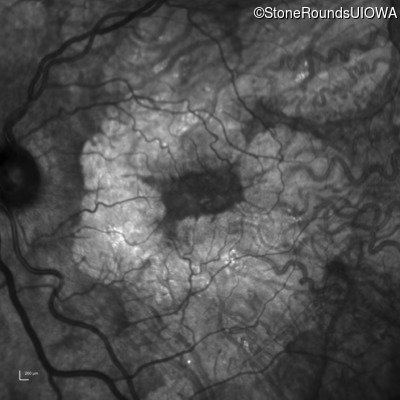

AR Stargardt Disease (IIA)

Age at visit: 51 years

This 51 year old woman first experienced some abnormality in her distance vision when she was 27 years old. She feels that her vision has been stable since that time.

Diagnosis & molecular findings

Disease Gene Allele 1 variant(s) Allele 2 variant(s) Inheritance mode

AR Stargardt Disease ABCA4 Gly1507Arg GGG>AGG IVS42+1 G>A AR